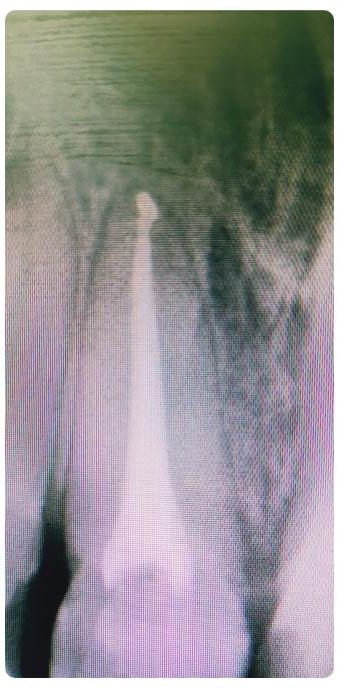

Dobrze przeprowadzony zabieg implantacji natychmiastowej daje efekty jak na pozostałych zdjęciach! Na każdym etapie leczenia mamy pełną kontrolę nad wszystkimi aspektami przyszłej odbudowy protetycznej – można powiedzieć, że zachowujemy to, co najtrudneijsze do odtworzenia, czyli kształt dziąseł.

Cytując Michała Mokijewskiego: „Pacjent przychodzi po idealny ząb, a nie po implant”.

Tylko implantacja natychmiastowa pozwala nam uzyskać taki efekt w zaledwie 3 wizyty.